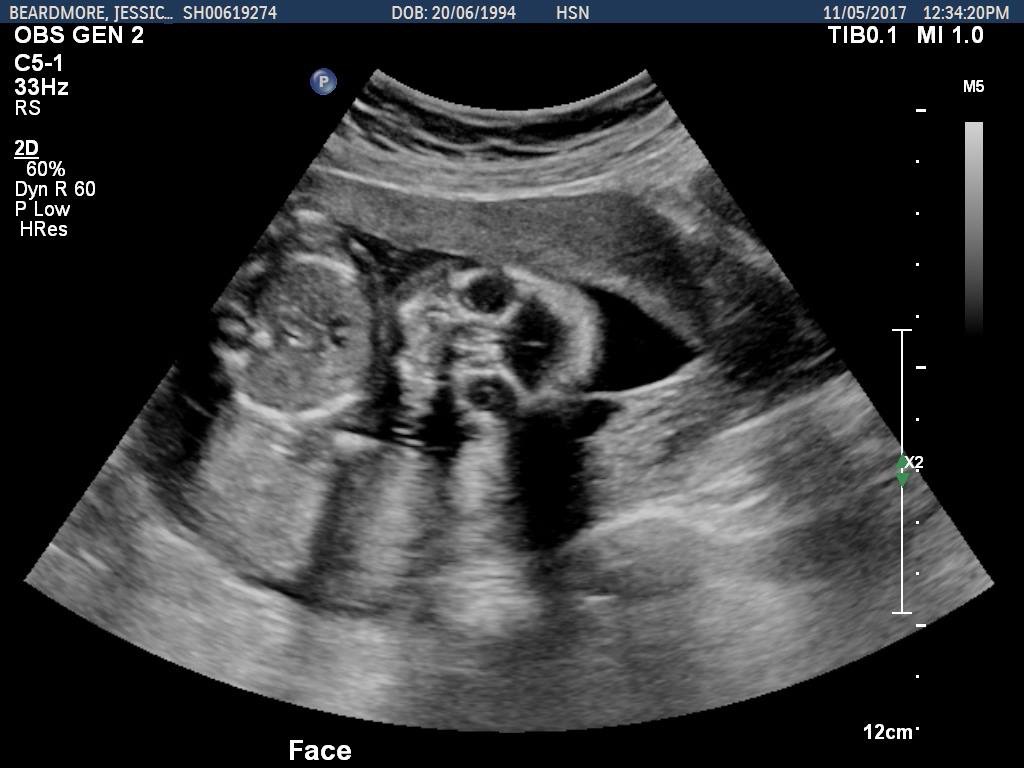

Can anybody guess a gender from these pictures? :) Come on mommies!! Heheh! Head shots and head/body.

Sorry no gender clues